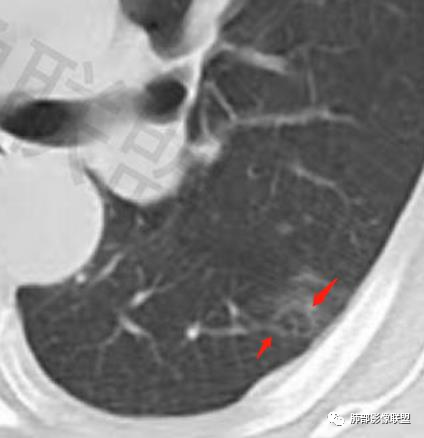

类圆形,边缘稍平直,周围晕中细微毛刺,密度均匀,均匀强化,血管走形自然,稍牵拉扭曲,支气管在近端堵塞

多发类似结节

结节周围有磨玻璃影,边界似清不清的,但是总体不如炎性晕征那么模糊;